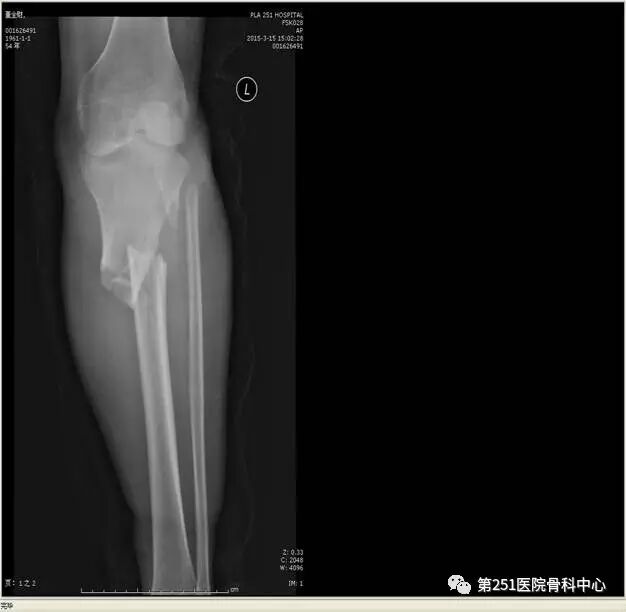

病例2:男性,44岁,车祸伤,双侧胫腓骨骨折(左侧)。

![]()